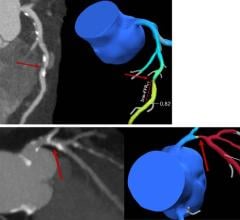

Founded in 2007, Therenva supports physicians in planning and performing minimally invasive endovascular interventions through innovative imaging solutions. The current portfolio includes EndoSize and EndoNaut, a patented solution for intra-operative 3-D navigation and localization of devices providing more confidence, accuracy, and visual comfort during catheterization procedures.

By bundling the leading C-arms of Ziehm Imaging and the EndoNaut solution, physicians already benefit from advanced 3-D intra-operative navigation for optimal guidance in endovascular interventions.

“Joining forces with Ziehm Imaging as innovation leader in mobile C-arm technology is a great opportunity for us to make our software devices available to physicians globally,” said Cemil Göksu, Co-founder and CEO of Therenva. “A deeper soft- and hardware integration will allow us to develop solutions that will set new standards in image fusion and 3-D navigation to provide clinicians with powerful yet seamless workflows supporting their patients’ treatment.”

Therenva has designed advanced and user-friendly imaging software toolsets for cardiovascular procedures since 2007. The unique EndoSize 3D case planning software has become an essential tool in the daily practice of many physicians and healthcare professionals. By widening the skills of the users and their abilities to plan cases quickly and accurately, EndoSize saves time and improves patient care.